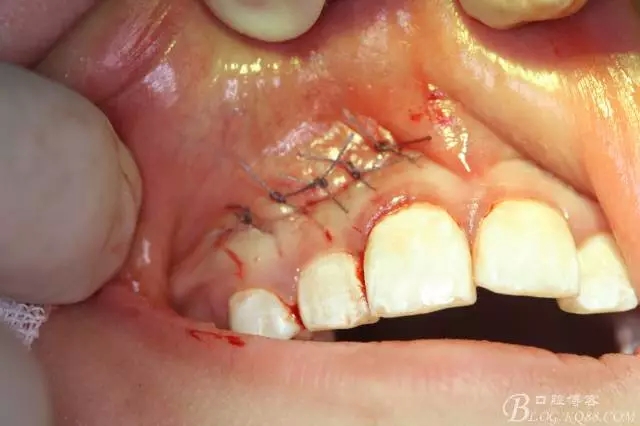

病例資料: 患者、柴xx、女、16歲。??茩z查及病歷如下圖: 患者同意我院正畸科建議,遂轉(zhuǎn)診倒外科。術(shù)前簽知情同意書。 治療過程: 圖1.術(shù)前的CBCT檢查:13阻生,疑為含牙囊腫??v剖面顯示12牙根吸收至根尖1/3。 圖2.局部麻醉下 。行唇側(cè)弧形切口,12松動(dòng)不到1°。 圖3.翻瓣、暴露骨面。 圖4.去骨、 暴露13牙冠 圖5.去骨、逐漸顯露13。 圖7.拔除13. 圖8.摘除囊壁 圖9.必須完整剝離囊壁。 圖10.摘除囊壁后形成的骨腔 圖11.超聲骨刀12根尖倒預(yù)備 圖13. 消毒棉球骨腔內(nèi)隔濕血液,紙尖干燥倒預(yù)備好的根管 圖14. 紙尖無血即可 圖15。MTA倒充填 圖16.骨腔填塞膠原蛋白海綿 圖17.拔除的13及摘除的囊壁 圖18.縫合 圖19.術(shù)后x線根尖片影像:MTA封閉根尖